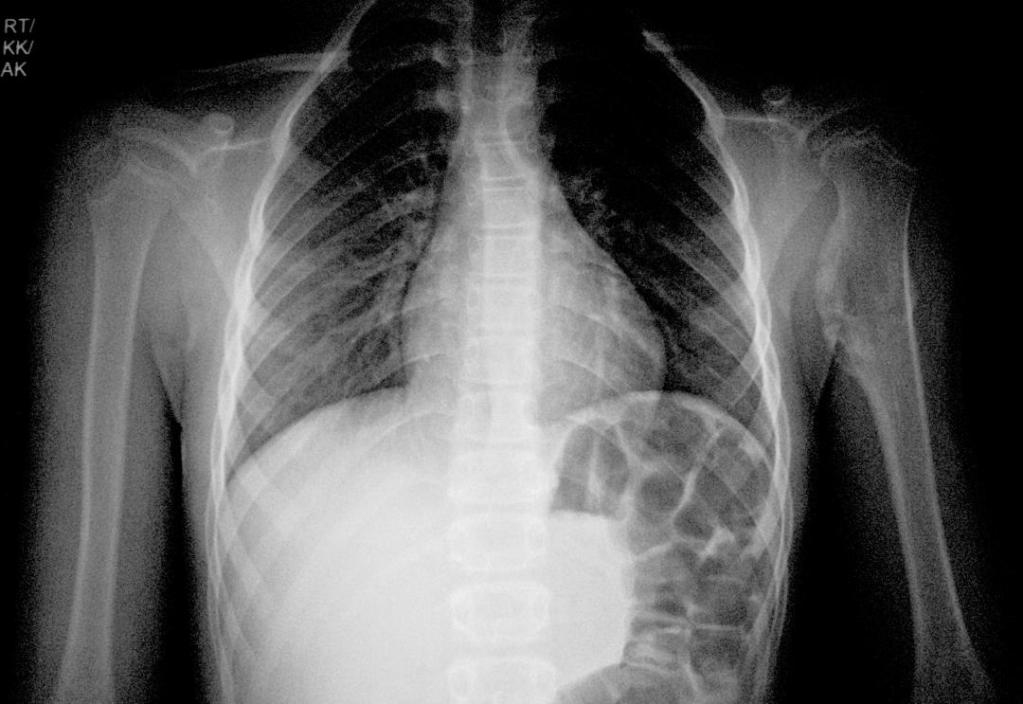

X-ray

Shows a bony swelling over upper third of the arm bone humerus of the left side Features BENIGN SESSILE tumour (non-pedunculated)

Osteochondroma upper third humerus of left side

AP view